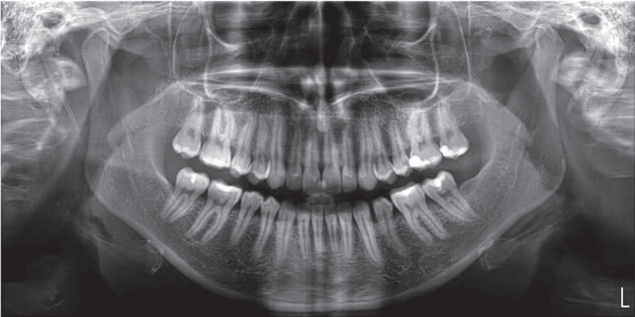

Hyperion X5全景、头颅和X射线体层摄影设备

Hyperion X5不断进化发展,现在头颅及3D拍摄也来到您的面前。这边在整个拍摄过程中快速易用,确保了高分辨率的3D和2D图像、低辐射时间以及实时诊断所需的快速数据处理,改善医患沟通。新的虚拟控制面板简化了拍摄流程,并引入了上颌窦容积检查和正交全景图像的新程序。由于3D传感器模块的自动伺服控制运动,较短的检查时间确保了连续的愉快体验。